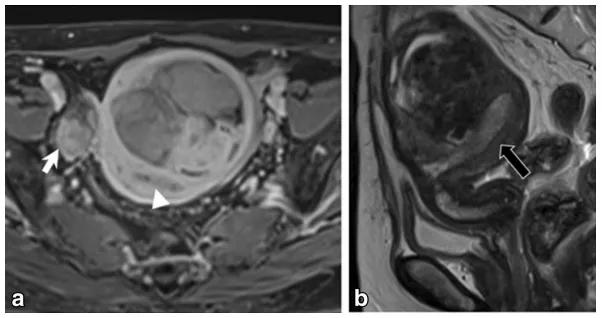

女,70 岁,卵泡膜细胞瘤。图 a 增强扫描显示右侧卵巢肿物(白箭),同时子宫内膜增厚(图 a 白箭头及图 b 黑箭)。

女,68 岁,左卵巢 Brenner 瘤。T2WI 显示左侧卵巢巨大低信号肿物(图 a),CT 扫描显示 8 年后肿物增大、多发钙化、发生囊变(图 b)。